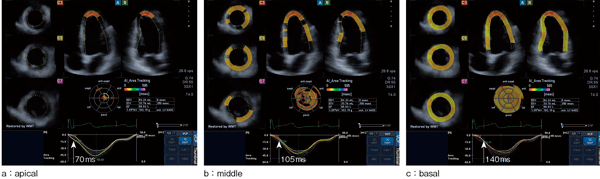

AIで解析が可能な壁運動指標としては,左室の構造的に直交するradial,longitudinal およびcircumferentialの各strainと,内外膜間のshear変形成分も加味された壁厚方向の指標である3D strain,および内膜面の面積変化率(area change ratio)がある。AIの表示形式としては,図1のような3D表示や,図3に示すようなPolar-mapおよびMPR画像上へのカラー重畳表示がある。

図3 area change ratioによるAI(健常例)

図3の健常例におけるarea change ratioを用いたAIでは,QRSの立ち上がりからの経過時間に応じて,心尖部から心基部にわたって円周方向にほぼ一様に収縮が伝播していく様子が示されている。